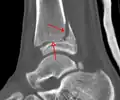

Fracture of both sides of the ankle with dislocation as seen on anteroposterior X-ray. (1) fibula, (2) tibia, (arrow) medial malleolus, (arrowhead) lateral malleolus

On X-rays, there can be a fracture of the medial malleolus, the lateral malleolus, and/or of the anterior/posterior margin of the distal tibia. The posterior margin (known as the posterior malleolus) is much more frequently injured than the anterior aspect of the distal tibia. If both the lateral and medial malleoli are broken, this is called a bimalleolar fracture (some of them are called Pott's fractures). If the posterior malleolus is also fractured, this is called a trimalleolar fracture.